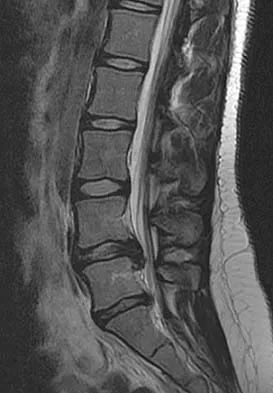

A 50-year-old man with no history of trauma reports new-onset back pain after doing some yard work the previous day. He reports pain radiating down his leg posteriorly and into the first dorsal web space of his foot. MRI scans are shown in Figures 3a through 3c. What nerve root is affected?

Detailed Explanation